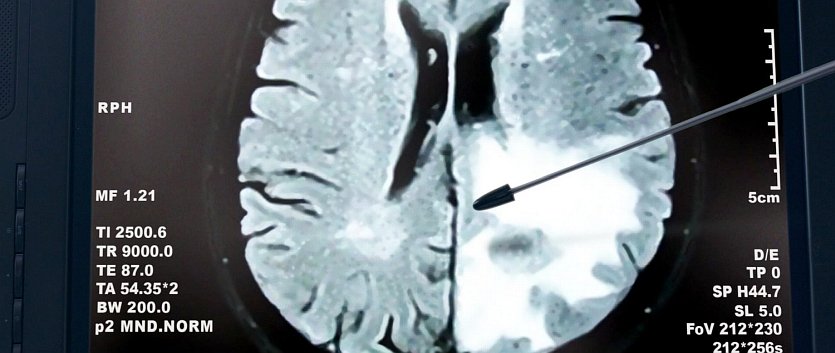

The Stolen Years (2013)

Name: The.Stolen.Years.2013_08854

Source: Blu-ray 1080p